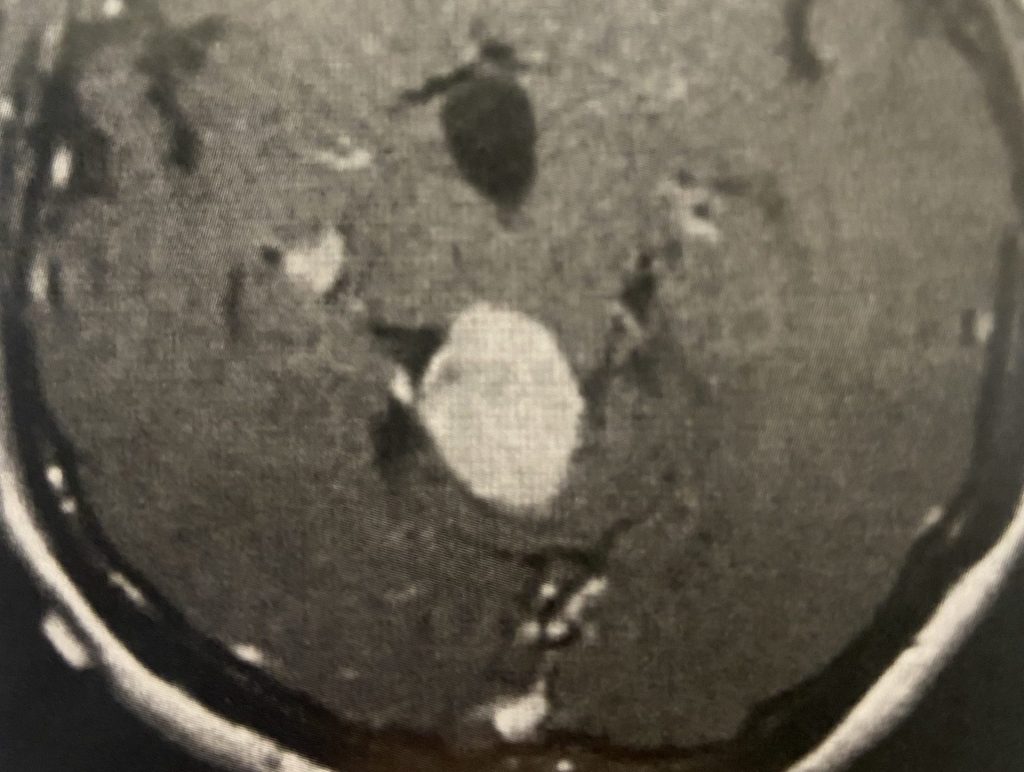

Brain:

Cerebellar Hemangioblastoma

Author: Michael Brisman M.D., F.A.C.S., Read More!